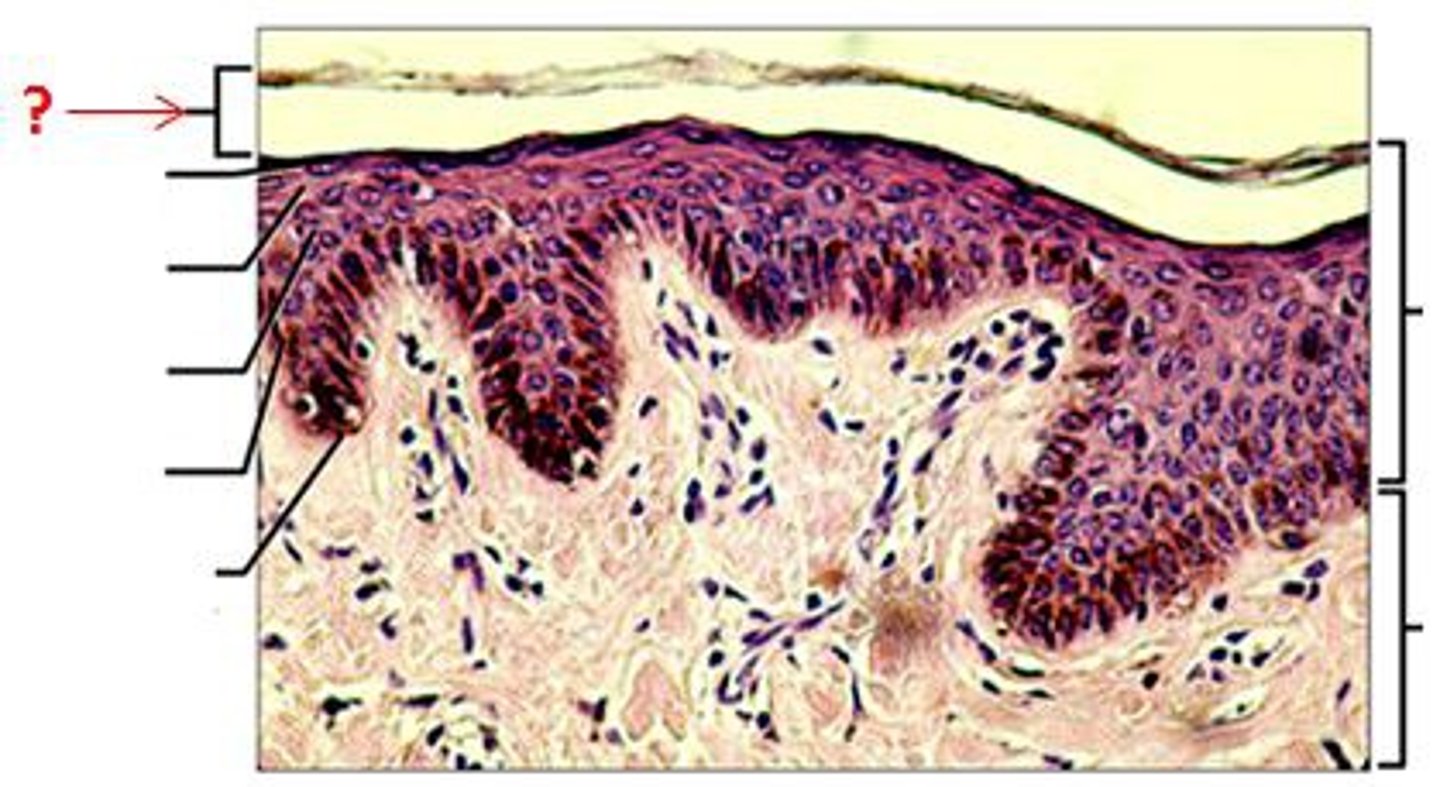

Epidermis

Outer layer of skin

stratum corneum

outermost layer of epidermis

stratum lucidum

Clear, transparent layer of the epidermis under the stratum corneum.

stratum granulosum

a layer of the epidermis that marks the transition between the deeper, metabolically active strata and the dead cells of the more superficial strata

stratum spinosum

stratum basale

the deepest layer of the epidermis consisting of stem cells capable of undergoing cell division to form new cells

Dermis

Inner layer of skin

papillary layer

outer layer of the dermis, directly beneath the epidermis; made of loose connective tissue

reticular layer

The deeper layer of the dermis that supplies the skin with oxygen and nutrients; made of dense irregular connective tissue

dermal papillae

a fingerlike projection of the dermis that may contain blood capillaries or Meissner corpuscles (of touch)